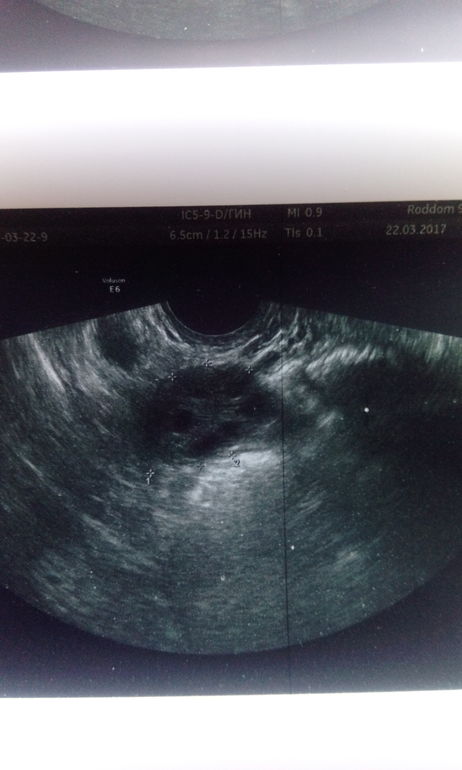

Посмотрите УЗИ

ФолликулометрияДелала на 9 день цикла. Обычно цикл 33 дня( может и больше до 35), но чтоб 26 дней ( как в этот раз)для меня это нонсенс. В итоге гормоны 2 фазы получилось неправильно сдала, что так рано дела начались и шли 7 дней, обычно 3-4 и свободна. Я так понимаю эндометрий совсем никакой и яичники МФя, да?